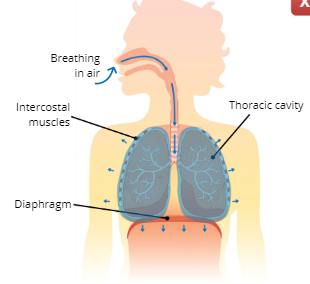

What are the 3 major respiratory muscles?

Diaphragm, External Intercostal Muscles, and Internal Intercostal Muscles

Diaphragm

a dome-shaped muscle below the lungs that separate the thoracic and abdominal cavity

External Intercostal Muscles

pull ribs upwards and outwards

Internal Intercostal Muscles

pull ribs downwards and inwards

Inhalation (inspiration)

Explain the Process of Inhalation (Inspiration)

The intercostal muscles and diaphragm contract, this causes the thoracic cavity to expand which increases lung volume, the increase in lung volume creates a suction that pulls air into the lungs